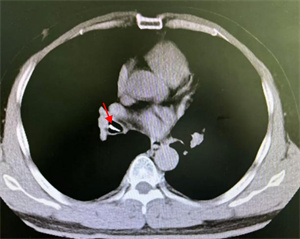

10月18日夜间急诊,来了一位14岁小患者,他在将手表零件放口中玩耍时,不慎吸入气管内。气管内异物是十分危急的,随时可能危及生命。小患者自觉胸闷不适,不时有咳嗽。急诊胸片和CT可以清晰地显示位于右中叶内侧段一长约2.3cm针形异物,两端较尖,急诊科医生程争启紧急联系呼吸与危重症医学科会诊,白克林主任考虑金属异物锐利可能损伤肺内血管造成大出血,准备急诊行内镜取异物。疼痛科、内镜室医务人员迅速反应,立即从家中赶往医院,争分夺秒做好各种术前准备工作。

白主任还邀请消化内科副主任吴斌、胸外科许涛医生一同到场,齐心协力保障患儿。然而,白主任用支气管镜反复多次查找,却始终没有发现异物,同时使用小探头超声内镜扫描,也一无所获。考虑有移位可能,白主任果断建议床旁摄片,进行气管镜下定位。时间紧迫,影像科技师汪津立刻带着机器来到气管镜室。经过摄片,发现金属异物显影在了胃泡里!